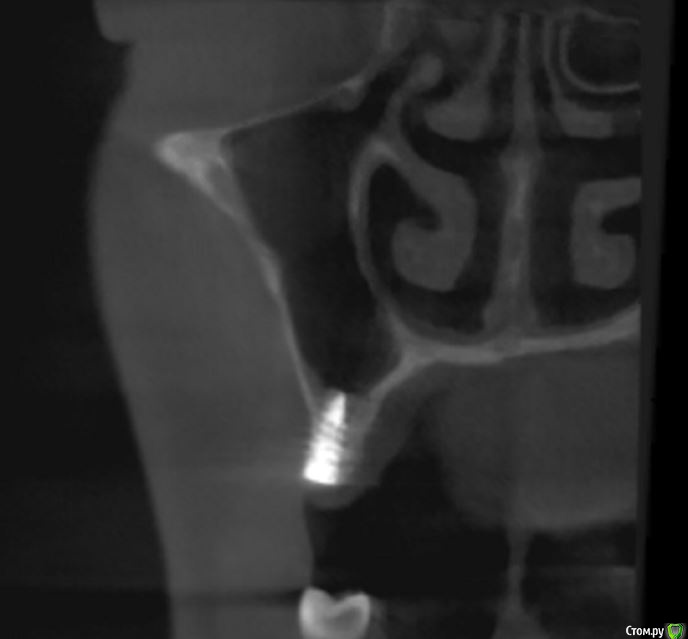

jm3300 Опубликовано 14 июля, 2016 Автор Поделиться Опубликовано 14 июля, 2016 выкладываю кт Ссылка на комментарий

умножающий печаль Опубликовано 14 июля, 2016 Поделиться Опубликовано 14 июля, 2016 Промыть пазуху через соустье, курсом. Я отправляю к ЛОРам. Антибиотикотерапия, гипосенсибилизация. Один из винтов вестибулярно без костной поддержки, на мой взгляд. 1 Ссылка на комментарий

red_butler Опубликовано 15 июля, 2016 Поделиться Опубликовано 15 июля, 2016 Пазуха чистая, Антон, какой винт на выход не понял?Может у пац аллергия ?На последних срезах, вестибулярно на 2/3 кости нет.Какая уж аллергия, если боль и отек 1 Ссылка на комментарий

умножающий печаль Опубликовано 15 июля, 2016 Поделиться Опубликовано 15 июля, 2016 Тоже не понял, вроде все хорошо стоят. Главное слизистые то в покое.Это пока в покое. Винт не покрытый костью, долго под мягкими тканями оставаться не будет. Неизбежна рецессия со всеми вытекающими. 1 Ссылка на комментарий

syrovovec Опубликовано 16 июля, 2016 Поделиться Опубликовано 16 июля, 2016 На последних срезах, вестибулярно на 2/3 кости нет.Ну может там вестибулярно мяса килограм) 1 Ссылка на комментарий